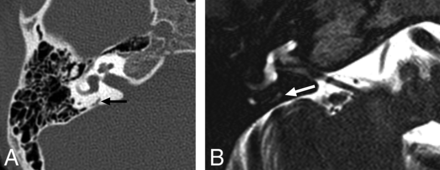

Axial MR imaging shows a normal ELD measuring 0.7 mm at the midaperture (arrow).

A, Axial HRCT shows a normal VA measuring 0.7 mm (arrow). B, MR imaging in the same patient shows the ELD measuring 0.5 mm (arrow).

A, Axial HRCT shows a normal VA measuring 0.4 mm (arrow). B, MR imaging in the same patient shows nonvisualization of the ELD.